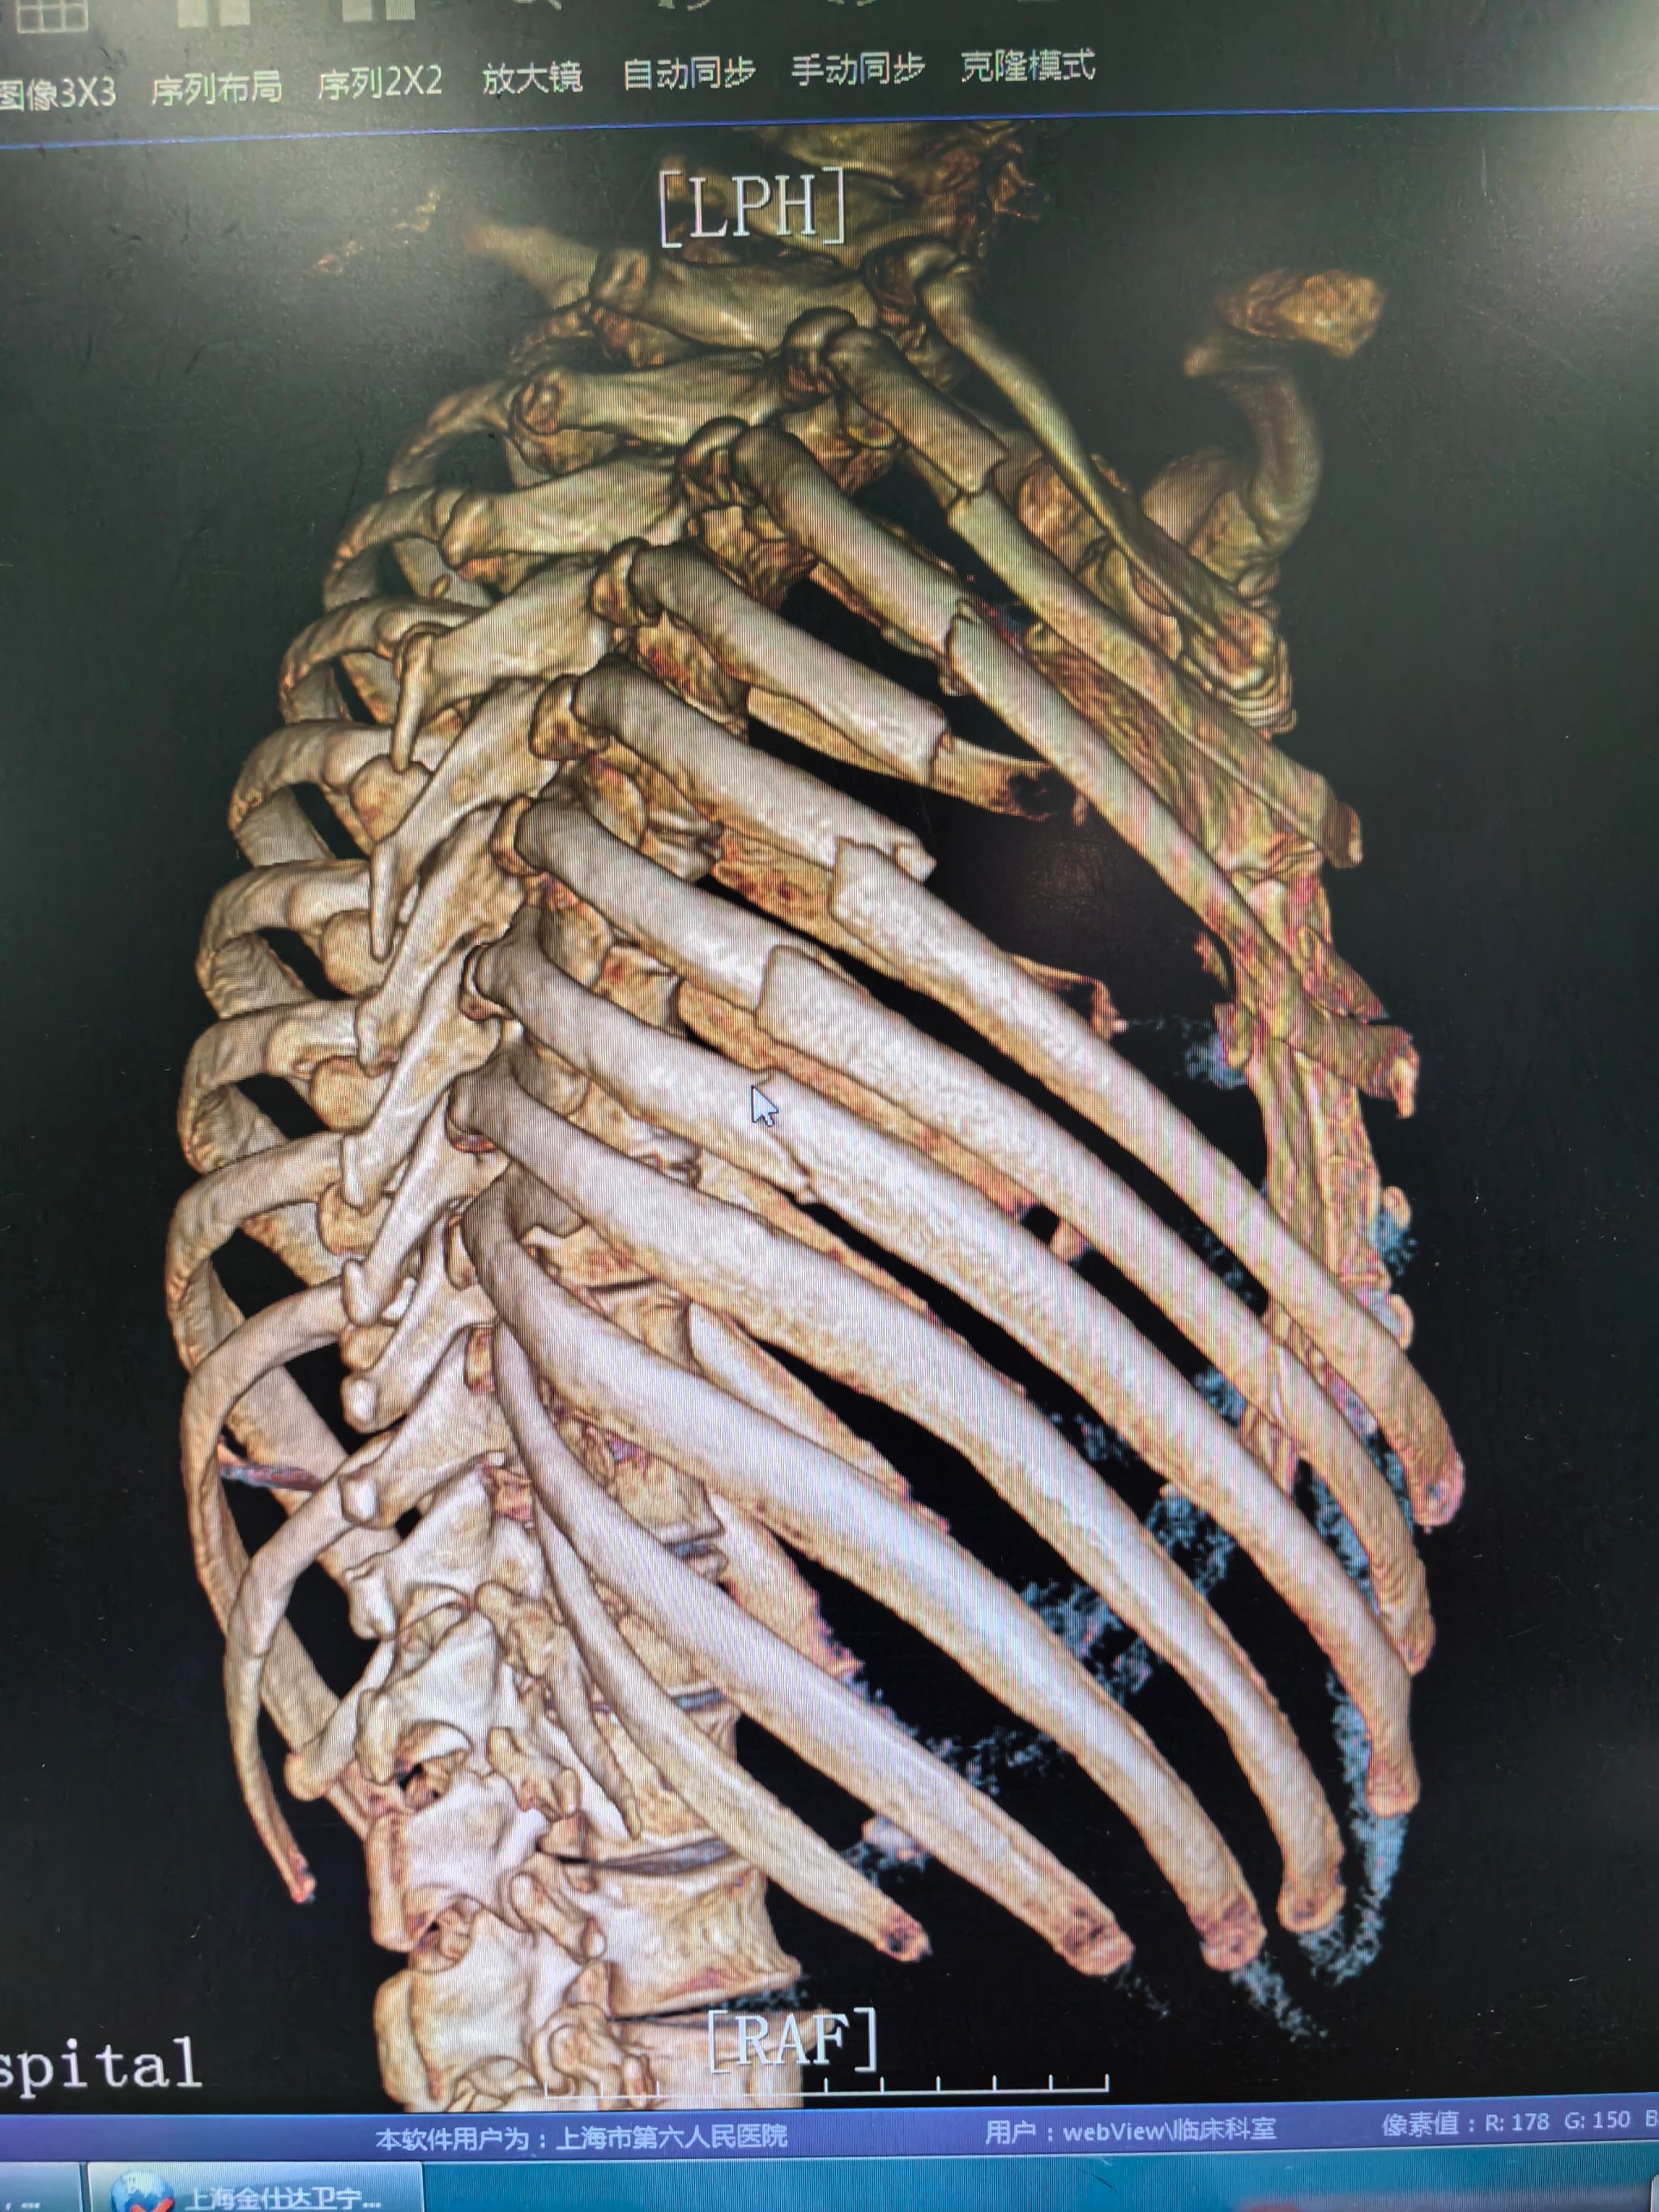

61岁的王先生和72岁的顾先生都是滑雪发烧友,在今年的雪季又驰骋在了雪白的世界。但极限运动总有风险发生,两位年过半百的运动健将不慎摔伤,造成了肋骨多根多段的骨折,且大多数骨折都位于肩胛骨后方。

这在以往的诊疗指南里,都是无需手术的,理由是骨折可以依靠肩胛骨的稳定,起到保护作用。但这一说法,在临床中是站不住脚的,哪怕是没有移位的骨折,只要骨质断裂都会造成胸廓不稳定,这种不稳定状态会导致每一次呼吸和上肢抬举时,都会出现严重的疼痛。给伤者正常的生活带来极大的影响,普通运动都无法恢复,更不要说再重新恢复滑雪运动。